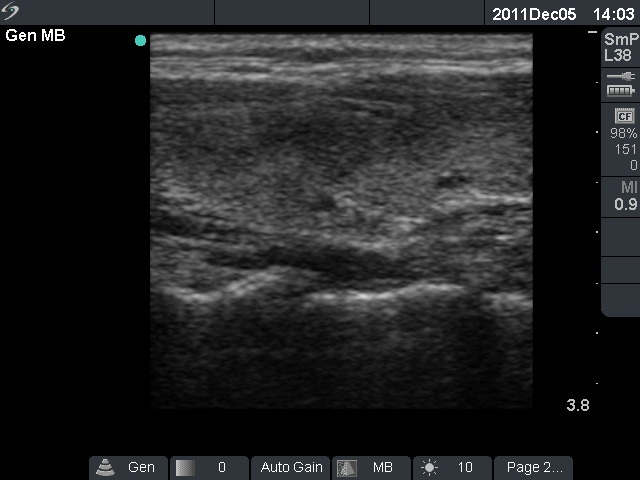

Ultrasonography: The right thyroid was echonormal and contained several small, insignificant lesions. There was a hypoechogenic lesion with blurred borders in the central and in the ventro-medial part of the left thyroid with increased intranodular blood flow.

We did not administer anti-inflammatory drugs because the patient was pregnant. Therefore, the hypoechogenic areas of the left thyroid decreased very slowly.